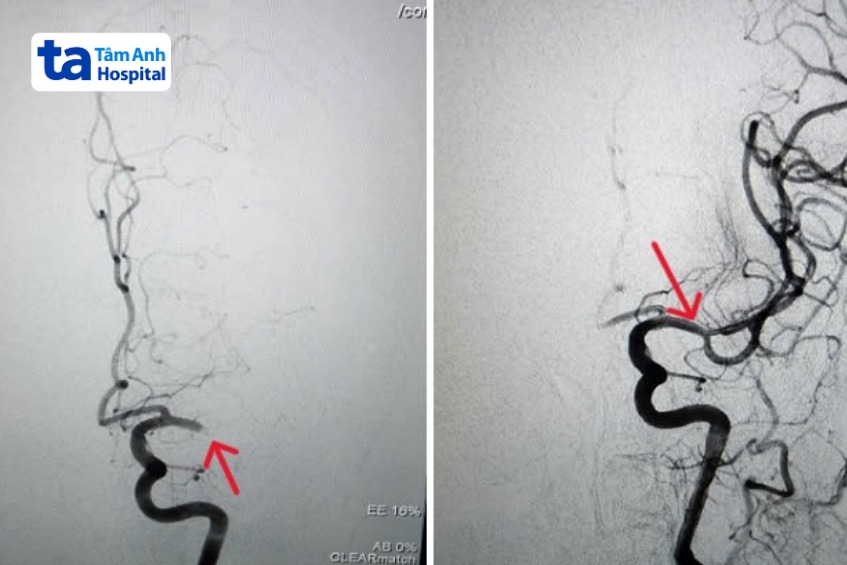

BS.CKI Dương Đình Hoàn, Trưởng Đơn vị Can thiệp Thần kinh, Trung tâm Chẩn đoán Hình ảnh và Điện quang Can thiệp, Bệnh viện Đa khoa Tâm Anh TP HCM, cho biết can thiệp nội mạch là phương pháp ít xâm lấn, hiệu quả cao và an toàn, nhất là với bệnh nhân đột quỵ cao tuổi, rung nhĩ. Dưới sự hỗ trợ của máy chụp mạch máu số hóa xóa nền DSA hiện đại, ê-kíp can thiệp luồn ống thông nhỏ vào động mạch đùi tại vùng bẹn, bên trong có thêm vi ống thông siêu nhỏ được gắn dụng cụ chuyên dụng. Sau đó, di chuyển trong lòng mạch, nhanh chóng tiếp cận vị trí cục huyết khối ở não.

Từ đây, bác sĩ tiến hành hút toàn bộ huyết khối ra ngoài, giúp tái thông mạch máu não chỉ sau 15 phút can thiệp. Phương pháp này giúp giảm tối đa tổn thương não và hạn chế các khiếm khuyết thần kinh sau đột quỵ.